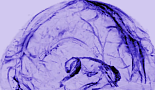

뇌에도 림프관이 혈관을 따라 존재한다면? 면역세포가 뇌의 림프관을 따라 움직이며 활발하게 면역작용을 하며 각종 노폐물이 배출되는 모습이 그려진다. 뇌의 면역시스템에 대한 생각을 근본적으로 바꾸는 개념이다. 2015년 독립된 두 연구팀이 쥐에서 처음으로 발견된 '뇌속 림프관의 존재', 당시 뇌는 면역작용이 거의 일어나지 않는 면역특권지역이라는 고정관념을 완전히 뒤엎으면서 이목을 끌었다. 그리고 인간에서도 림프관이 확인됐다. 미국국립보건원(NIH) 산하의 국립신경질환연구소(NINDS)의 Daniel S. Reich 선임연구원과 a